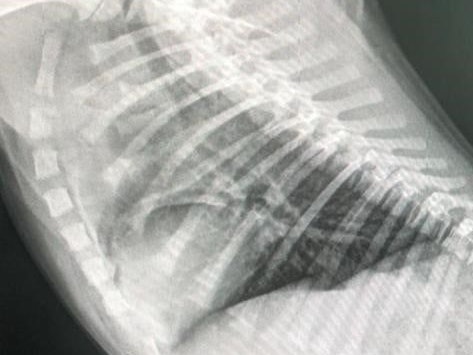

Einer der Welpen, die kleine "Ema", bereitet den Mitarbeitern große Sorgen. Der inzwischen zwölf Wochen alte Welpe wurde aufgrund der mangelnden Entwicklung besonders genau beobachtet. Neben einer Herzstörung wurde nun auch eine Einbuchtung in der Trachea festgestellt. "Mit Hilfe unseres großen Tierfreundes und Veterinärmediziners Dragan Lorinson werden wir Ema nun die bestmögliche Behandlung zukommen lassen", heißt es auf der Seite des Tierschutzvereines. Doch für dieses Unterfangen und die nötigen Medikamente wird Hilfe benötigt (sh. Spendenaufruf weiter unten im Text).

Bei dem Welpen wurde eine Einbuchtung in der Trachea festgestellt.

Tierschutzverein St. Pölten